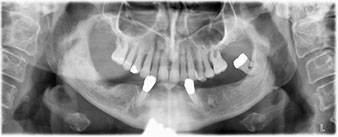

The 64-year-old patient presented with residual dentition of teeth 38, 33 and 43 and a clasp denture in the mandible (Fig. 1 and 2).

residual dentition

Fig. 1

Fig. 2